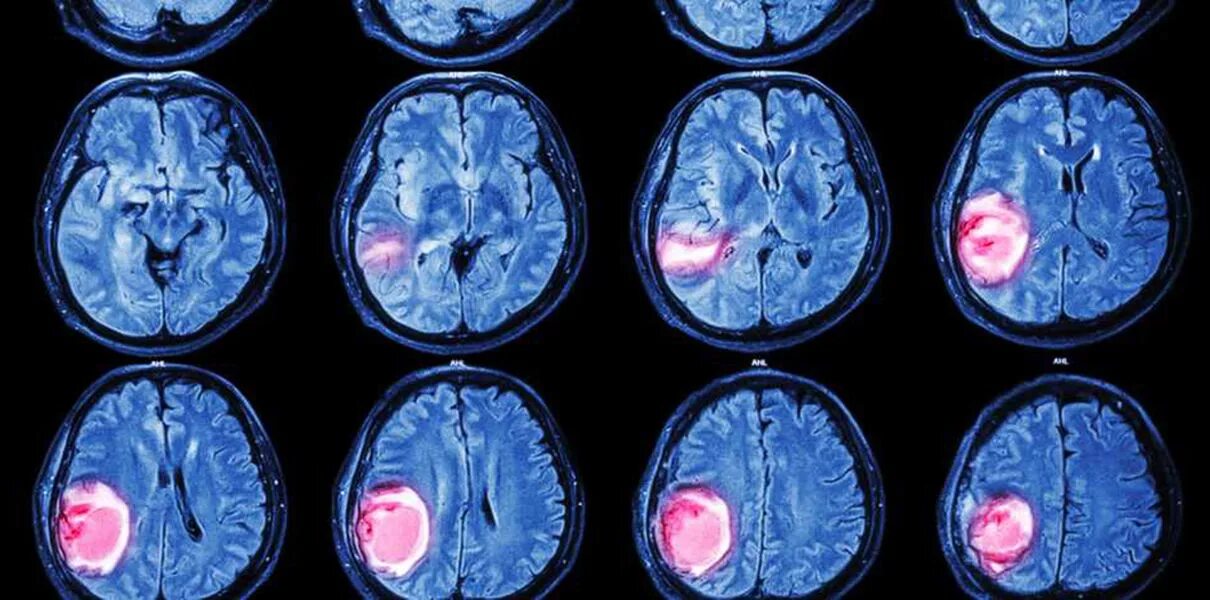

Терапия при опухоли мозга